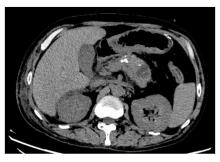

Zhongwei ZHOU,Wei DU,Yu NING,Jing YU,Fengyou GUO,Xueliang YANG.

SMARCB1/INI1-deficient undifferentiated pancreatic carcinoma: A case report and literature review

[J]. Journal of Jilin University(Medicine Edition), 2026, 52(2): 523-529.